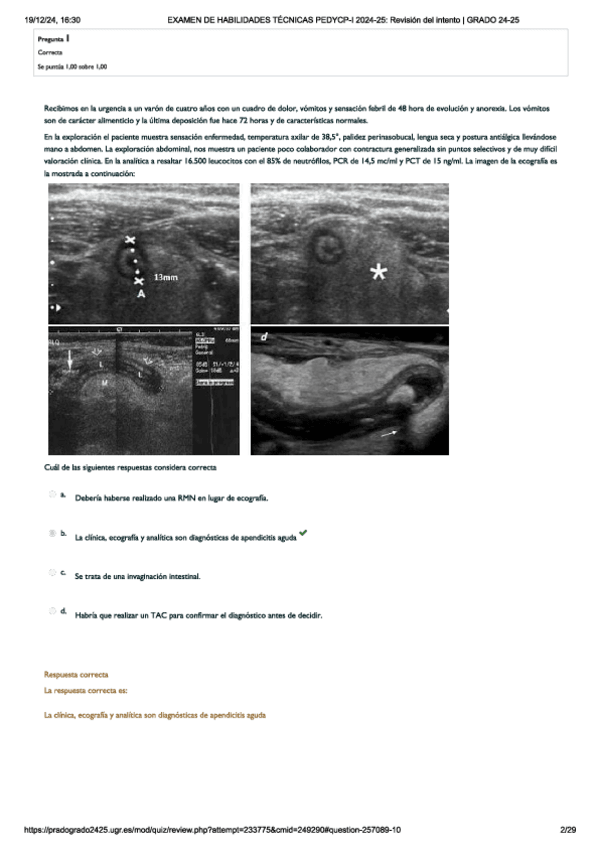

He publicado nuevos examenes de 5º PEDIATRÍA Y CIRUGÍA PEDIÁTRICA I: examen-practicas-pediatria.pdf

29 páginas

He publicado nuevos examenes de 5º PEDIATRÍA Y CIRUGÍA PEDIÁTRICA I: Practico-Pediatria.pdf

31 páginas

He publicado nuevos examenes de 5º PEDIATRÍA Y CIRUGÍA PEDIÁTRICA I: Ex-PRAC-PEDIATRIA-24.pdf

20 páginas